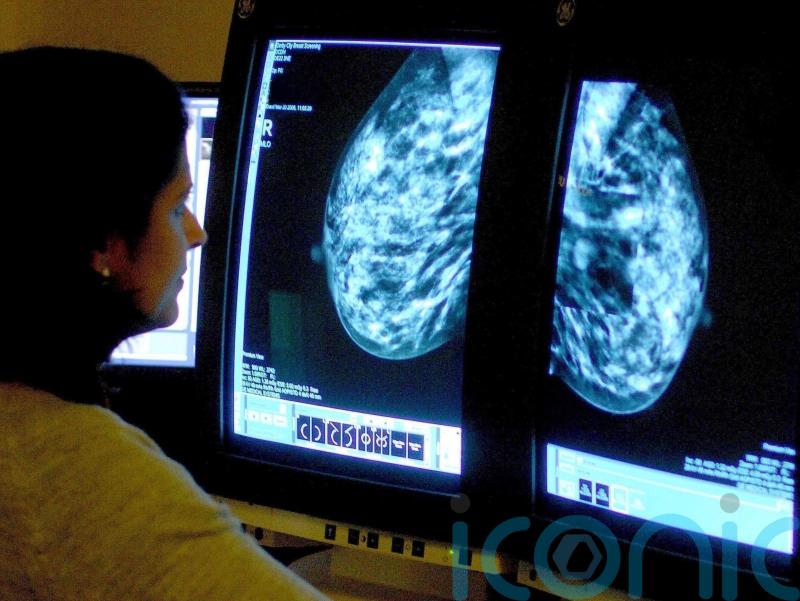

The importance of red flag referrals and screening routes for early diagnosis of cancer to improve survival rates for people in Northern Ireland has been highlighted in a report.

The study from the Northern Ireland Cancer Registry (NICR) at Queen’s University Belfast used research conducted on patients diagnosed between 2018 to 2020.

The Routes to Diagnosis report shows a strong relationship between a patient’s route to diagnosis and how advanced their cancer was at diagnosis.